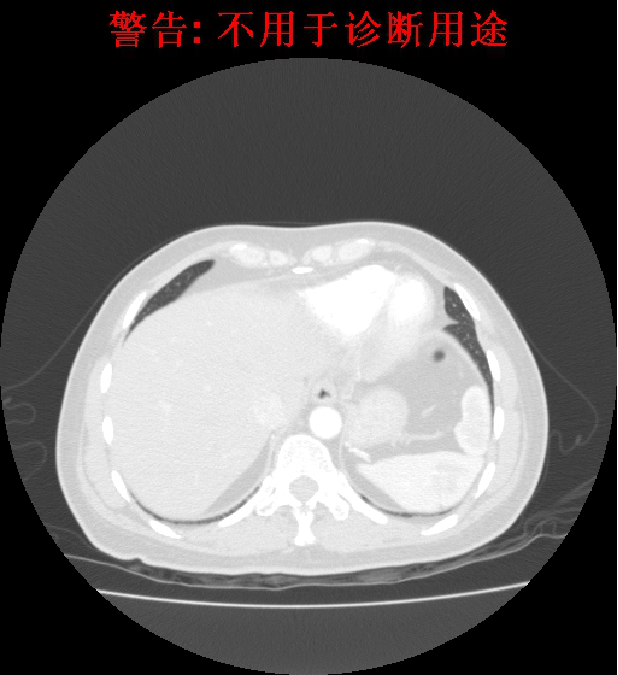

2012-3-21影像